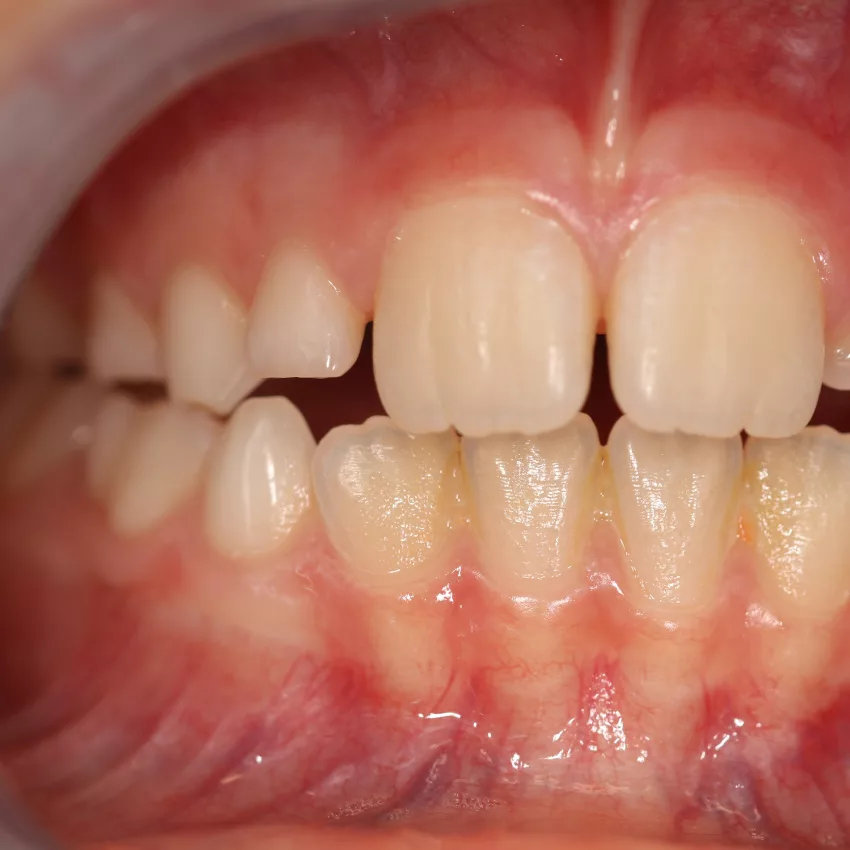

Die Entscheidung für eine Zahnspange bei Kindern wird häufig von ästhetischen Überlegungen begleitet. Schiefe Zähne oder sichtbare Lücken sind für Eltern und Kinder oft ein Anlass, frühzeitig über eine kieferorthopädische Behandlung nachzudenken. Aus medizinischer Sicht steht jedoch nicht das äußere Erscheinungsbild, sondern die Funktion im Vordergrund.

Eine Zahnspange ist dann medizinisch sinnvoll, wenn Fehlstellungen den Biss, die Kaufunktion oder die Entwicklung des Kiefers beeinträchtigen. Unbehandelte Fehlstellungen können langfristig zu Problemen beim Kauen, Sprechen oder zu einer erhöhten Abnutzung der Zähne führen. In solchen Fällen ist eine frühzeitige kieferorthopädische Abklärung wichtig, um den optimalen Behandlungszeitpunkt festzulegen.

Nicht jede Zahnfehlstellung erfordert jedoch sofort eine Behandlung. In manchen Entwicklungsphasen können sich Zahn- und Kieferstellungen von selbst regulieren. Eine rein ästhetisch motivierte Zahnspange ohne medizinische Notwendigkeit sollte daher immer kritisch geprüft werden.